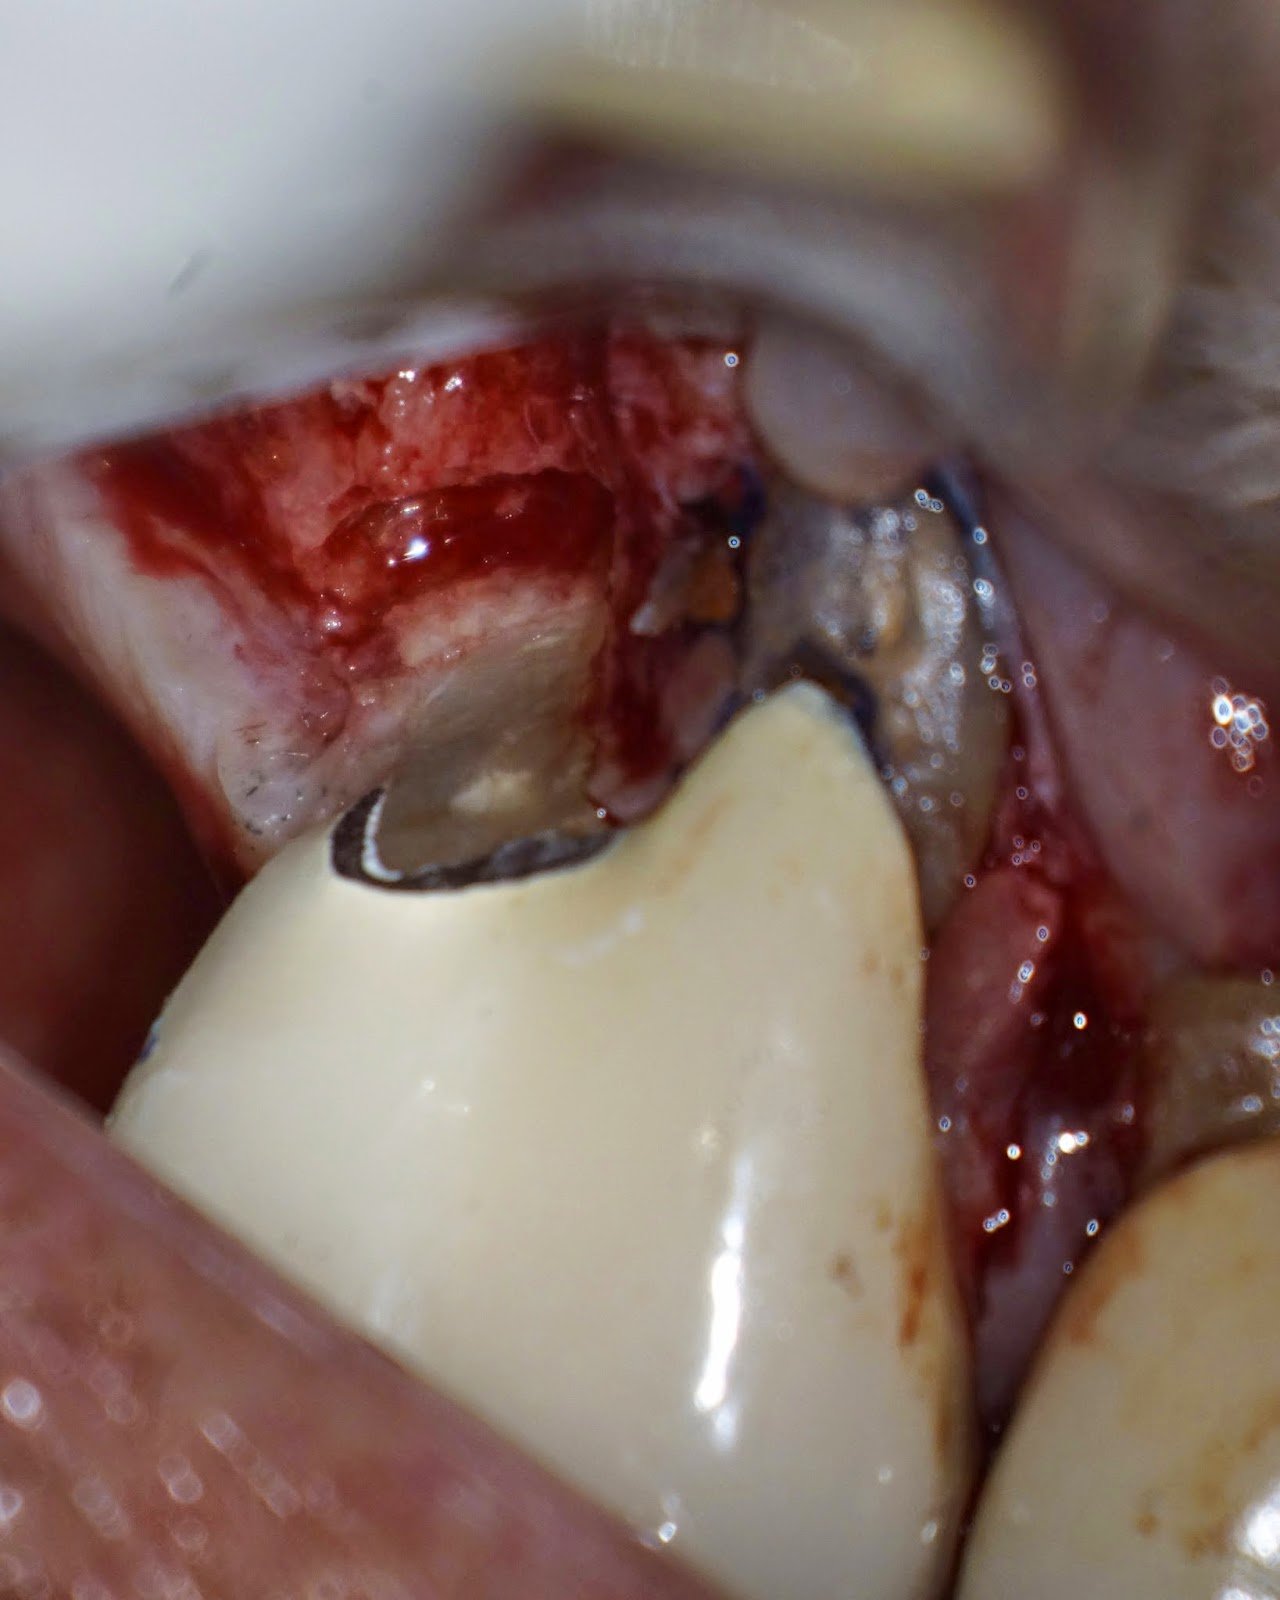

Root amputation is not a commonly performed procedure in my practice, but when it is, I like for it to look like this. In this case, the tooth is non-mobile – despite the bone loss around the DB root. While the distal margin is open, it is not carious and patient is not planning to replace the crown at this time. Pt understands that this procedures extends the life of the tooth. I explain that the short term prognosis is good. If the tooth does well, then replacement of the crown can be considered.